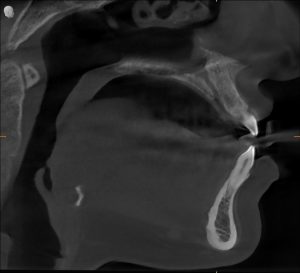

Radiology: The Airway Was Normal — The Function Wasn’t

Not all breathing problems come from narrow jaws.

CBCT + cephalometric evaluation showed:

- Normal maxilla

- Normal mandible

- Adequate posterior airway space

Her anatomy was fine.

The issue was functional, not skeletal.